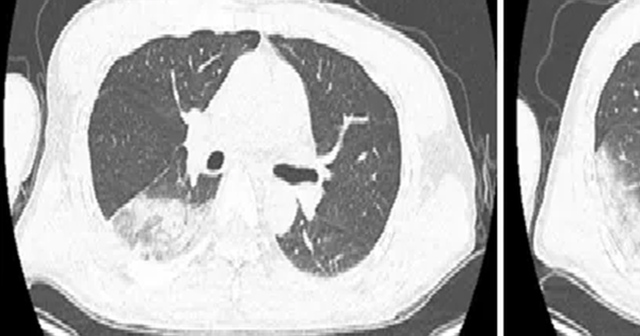

Kết quả kiểm tra cho thấy hai thuỳ phổi dưới đã viêm, chức năng gan thận đều tổn thương, chỉ số viêm tăng cao bất thường.

Khi bác sĩ truy lại tiền sử sinh hoạt, nghe tới chuyện “nuôi chim trong túi áo”, tổ chuyên môn lập tức nghi ngờ anh Lâm mắc bệnh Chlamydia psittaci (sốt vẹt).

Xét nghiệm chuyên sâu và giải trình tự gene mầm bệnh đã xác nhận đúng là nhiễm Chlamydia psittaci.